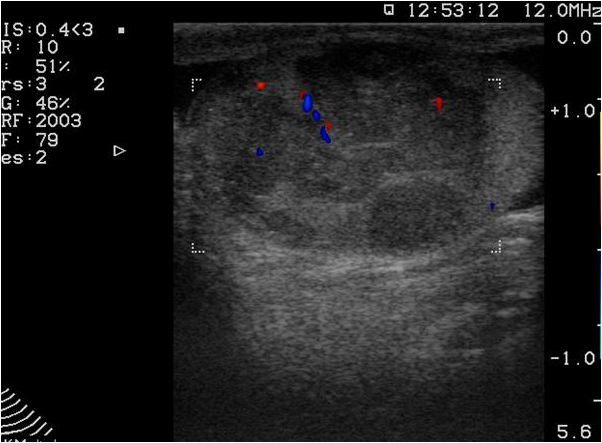

Ultrasonography (US), which is an extensively used and a widely available method, is often the first step in the diagnostic work up. During a regular abdominal US scan both kidneys are examined. Sensitivity of the US examination is significantly lower than of a CT scan, still important clinical questions can be answered with this technique. When a tumor is visualized, it is usually a hypoechoic, relatively well circumscribed mass.

Image

Figure 3. Kidney tumor on US